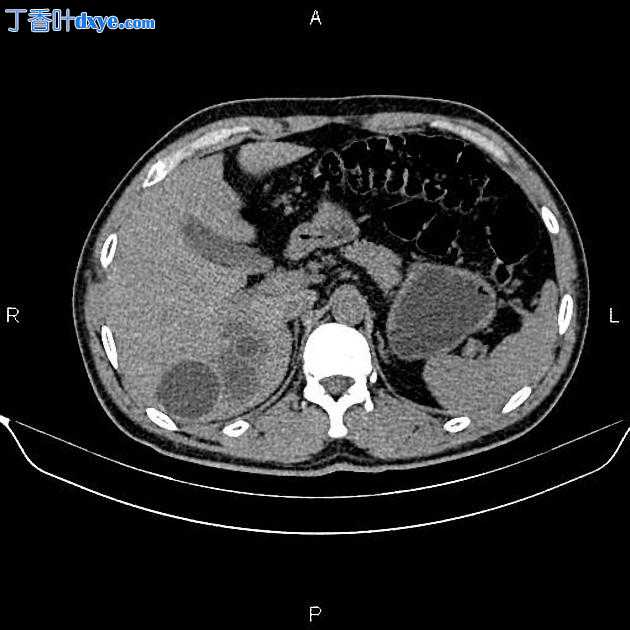

2.jpeg

Axial C+ arterial phase

在右肝叶小于 55 mm 处可见三个相邻的厚壁囊性病变。

此外,还描绘了一个直径为 15 毫米的低密度肝病灶,位于第 4 肝段(Couinaud 的命名法),显示早期外周、结节状强化和向心性充盈。特征与血管瘤最相容。